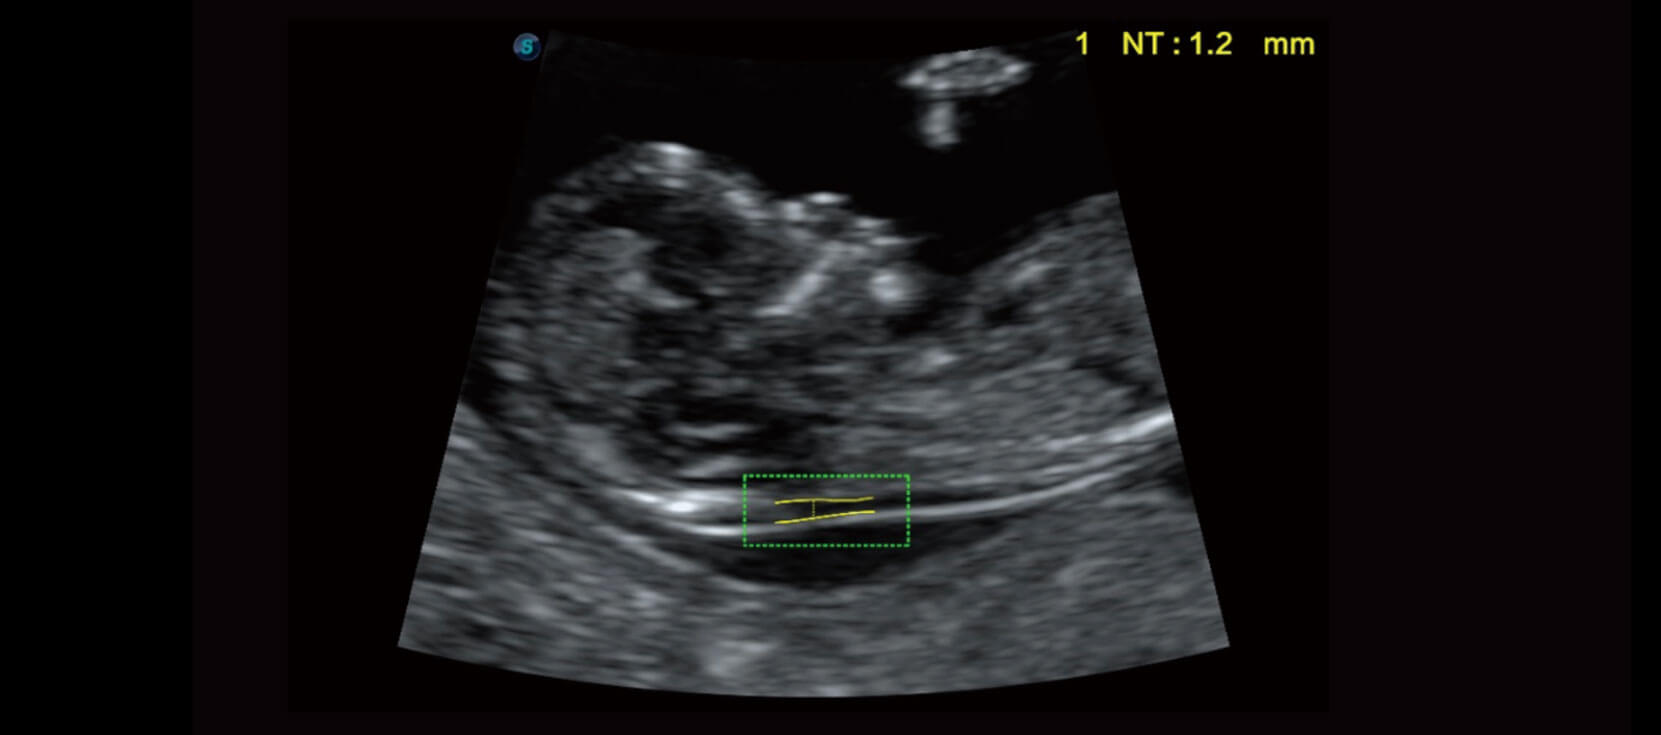

Auto NT

Tự động NT cung cấp các phép đo độ mờ da gáy bán tự động, tiêu chuẩn hoá trong hình ảnh 2D, giúp giảm sự phụ thuộc của người vận hành và kết quả.